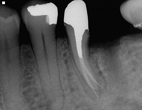

Conventional Treatment with Standard Core Restoration

Conventional endodontic treatment with alloy core build up